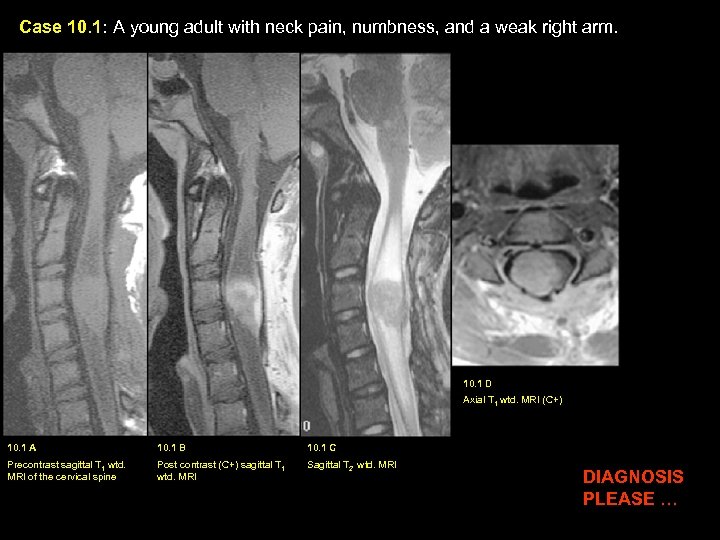

Case 10. 1: A young adult with neck pain, numbness, and a weak right arm. 10. 1 D Axial T 1 wtd. MRI (C+) 10. 1 A 10. 1 B 10. 1 C Precontrast sagittal T 1 wtd. MRI of the cervical spine Post contrast (C+) sagittal T 1 wtd. MRI Sagittal T 2 wtd. MRI DIAGNOSIS PLEASE …

Case 10. 1: A young adult with neck pain, numbness, and a weak right arm. C C D. A. B. C. Findings: : An inhomogeneously enhancing tumor (red arrow in B) is seen within the upper cervical cord. Large cysts (C) are seen both above and below the tumor, best seen on T 2 wtd. image C. Eccentric location of the tumor, more to the right of the cervical cord (yellow arrow) is shown on axial image D. Diagnosis: Astrocytoma

Astrocytoma of the Spinal Cord Incidence: Common intramedullary tumor particularly in children and young adults. Pathology: Usually low grade MRI Findings: · Eccentric location of tumor within the spinal cord · Multisegmental involvement · Variable degree of tumoral enhancement · Cysts are common · Hemorrhage is rare Treatment: · Complete resection of tumor is not possible due to infiltrative nature. Radiation therapy is also used for recurrence or growing tumors.